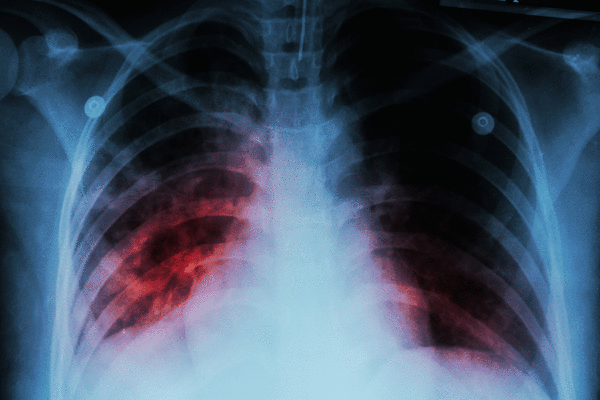

Tuberculosis is a respiratory disease caused by bacteria, according to the U.S. Centers for Disease Control and Prevention.

TB primarily affects the lungs and can spread to other parts of the body, such as the brain, spine, lymph nodes and kidneys.

According to the CDC, common symptoms of tuberculosis disease in the lungs can include:

— A bad cough that lasts three weeks or longer

— Pain in the chest

— Coughing up blood or sputum (phlegm) from deep inside the lungs